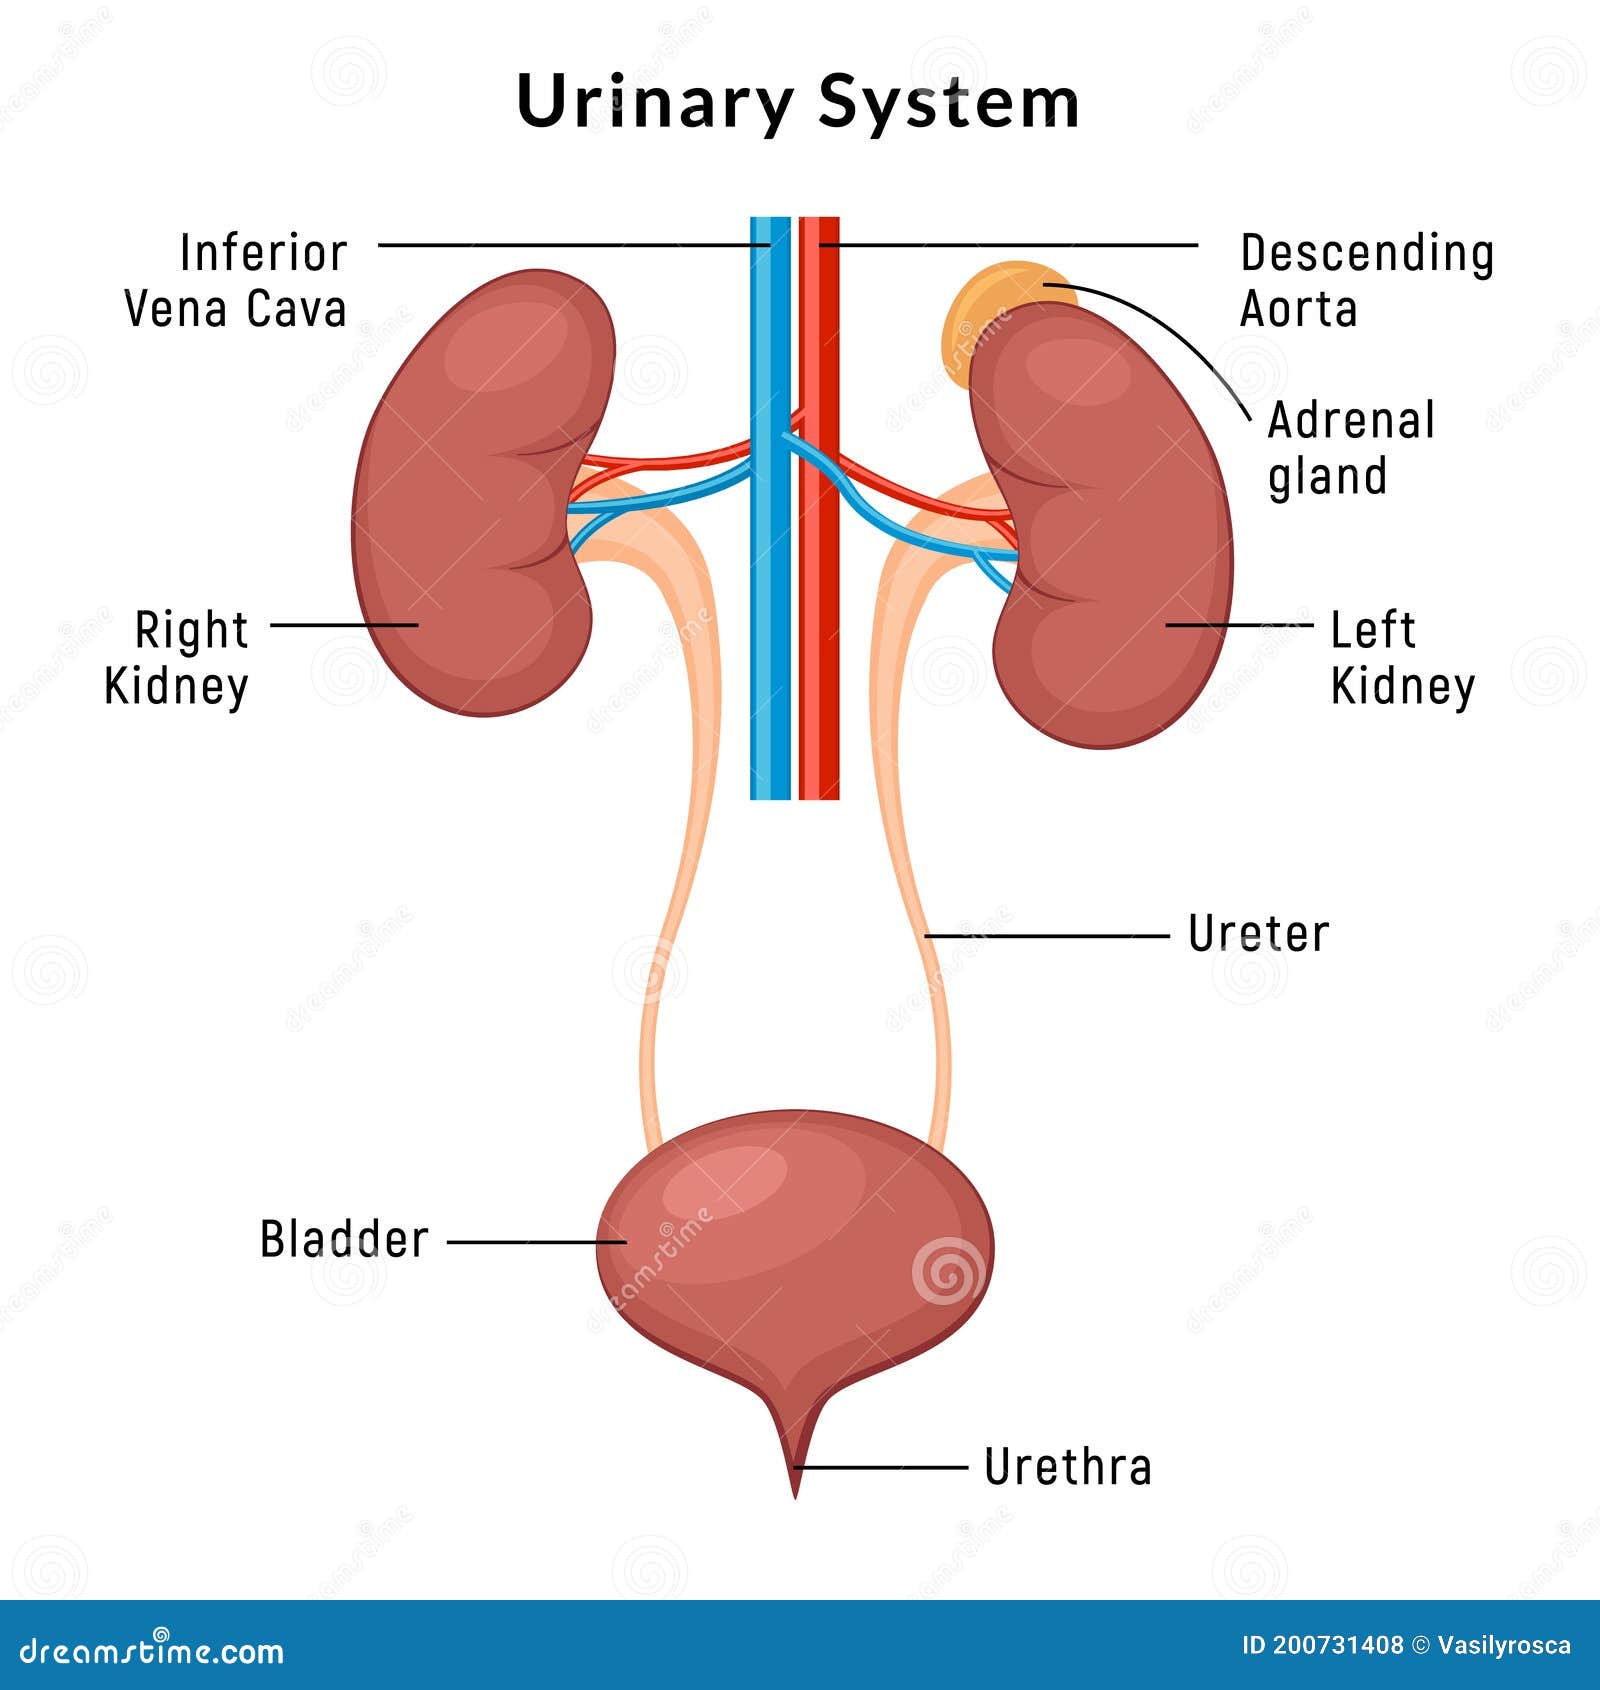

location of the bladder in the human body

Posts: location of the bladder in the human body